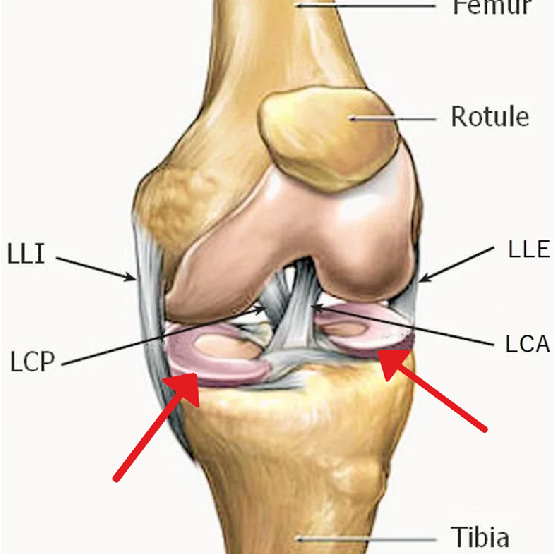

Information médicale complète à destination des patients Cette page a pour objectif de fournir une information claire, détaillée et approfondie sur le conflit fémoro-acétabulaire (CFA), également appelé femoroacetabular impingement (FAI). Elle s’adresse aux patients souffrant de douleurs de hanche, en particulier aux adultes jeunes et physiquement actifs, et vise à répondre aux questions les plus fréquentes concernant le diagnostic, les...